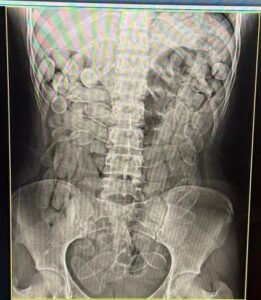

Ao serem abordadas, demonstraram nervosismo e uma delas acabou passando mal, vomitando uma cápsula de substância análoga à pasta base de cocaína. As duas foram encaminhadas à Santa Casa de Corumbá, onde exames de raio-x confirmaram que cada uma havia ingerido 102 cápsulas. A apreensão totalizou aproximadamente 2,2 quilos da droga.